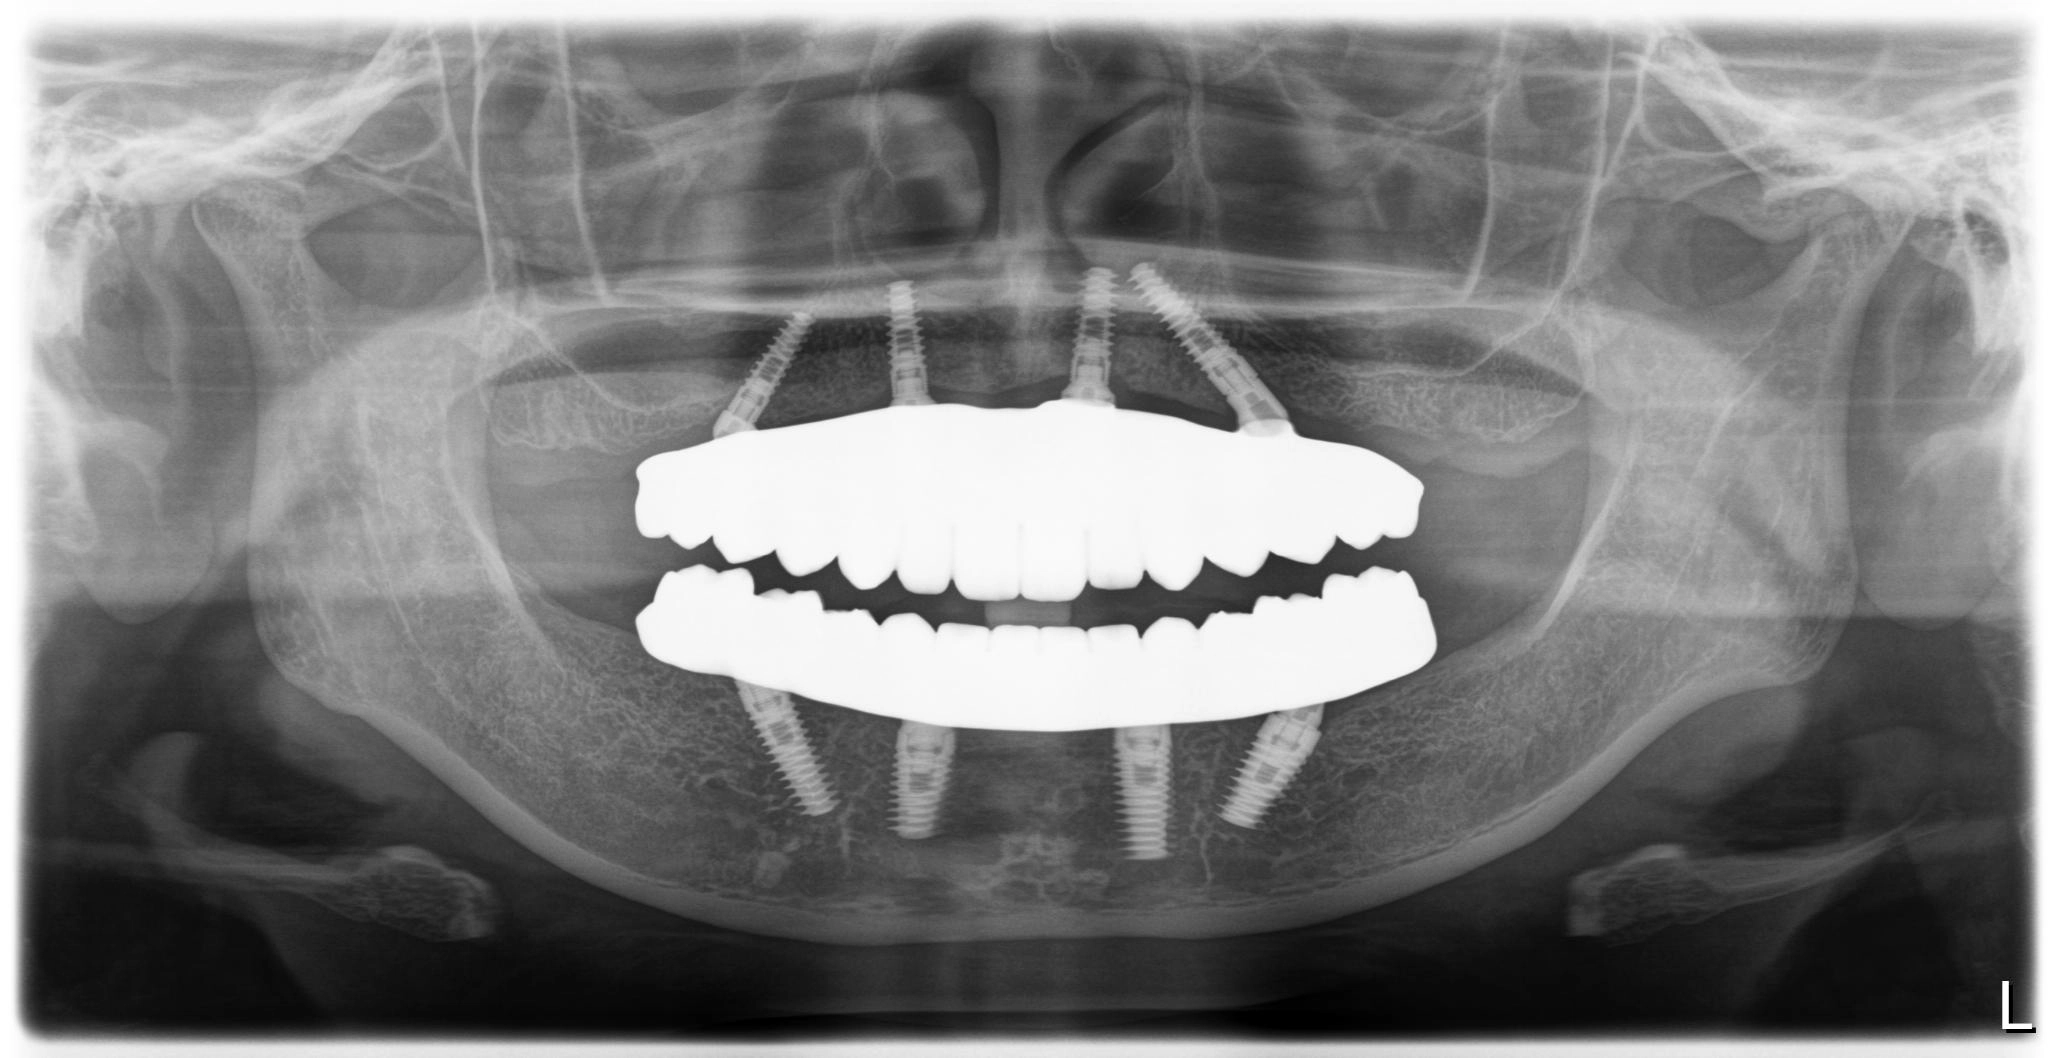

術前

術後

内容 :上下顎オールオン4ザイゴマ0

費用 :4,989,600円

※モニター価格

期間 :半年

リスク:出血・腫れ・痺れ・痛み